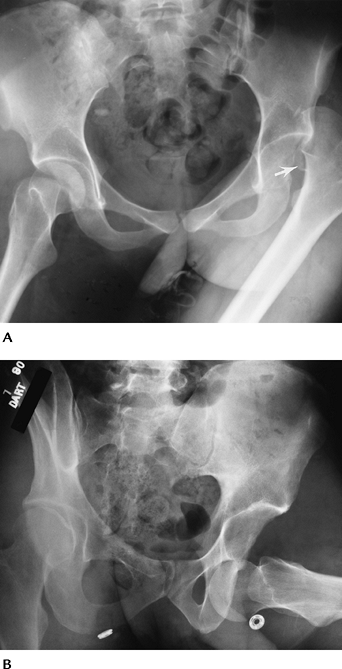

FIGURE 4-12 AP radiographs of posterior (A) and anterior (B) dislocations. Note the displaced femoral head fragment (arrow) in (A).

|